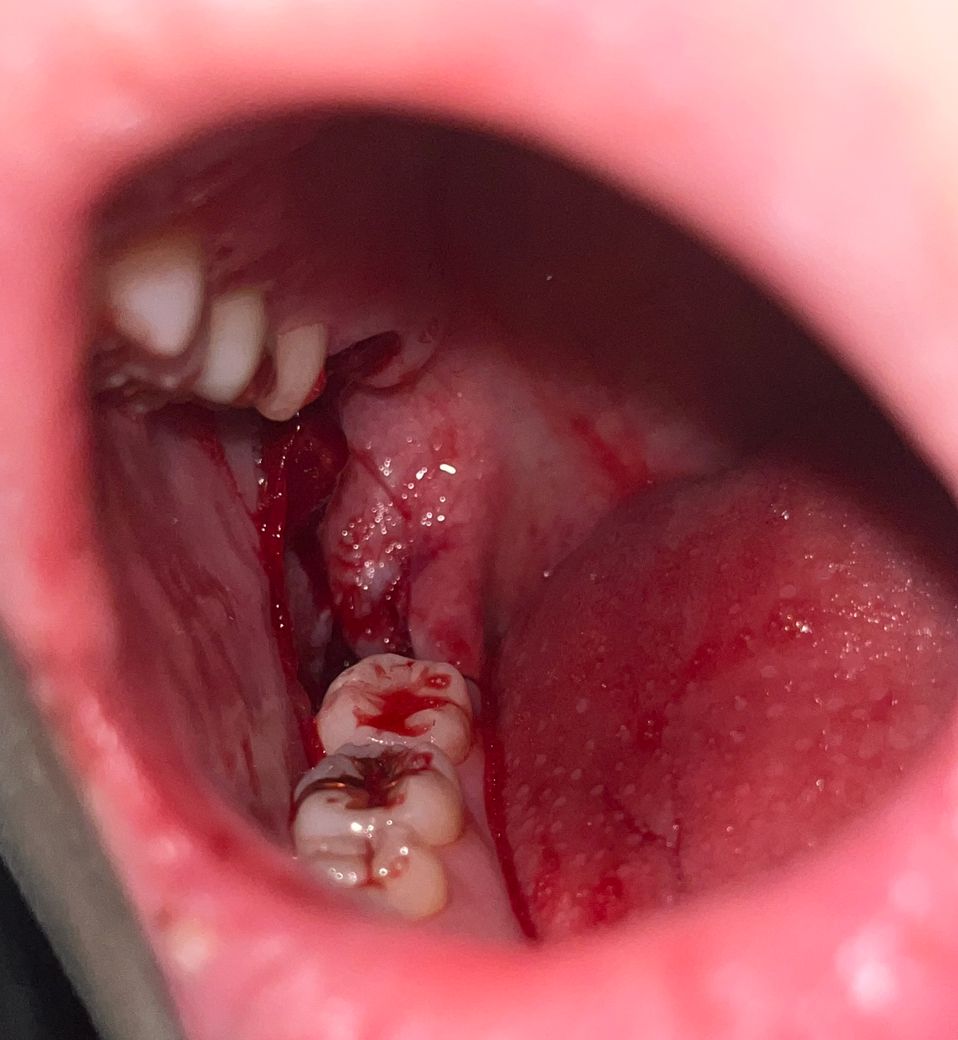

발치하고 거즈 2시간 물고 뺐는데 피떡 괜찮나요?

볼에 피떡 같은데 내려와있어서 신경쓰이는데 내일 소독 가긴 합니다ㅠㅠ 혹시나 더 지혈을 해야하는 상황인 것인지 ㅠㅠ 걱정됩니다ㅠㅠ 당장 치과 가봐야 하나요??

• 1번 째 사진

지금 당장 갈 필요는 없습니다. 피가 계속 조금씩 스며 나와 뭉처진 피떡(혈병)이 생겼습니다. 집에 꺼즈 있으면 다시 한번 꺼즈 무는 것이 좋습니다. 밤새 조금씩 피가 스며 나올 수도 있지만 그냥 두어도 됩니다. 내일 치과로 가서 소독해야 합니다.

피떡이 생기는 것은 정상적인 상황입니다. 피가 아직 많이 나오면 지혈을 더 하시고 피만 멎었다면 내일 가시면 됩니다.

피가 아직은 많이 나는거 같으니 거즈를 다시 꽉 깨물고 있어야될것같습니다. 지혈이 안되면 치과에 가셔서 후처치라도 받아보시는게 좋을것같습니다.

발치 구멍 밖으로 나온 피떡은 그냥 제거해주셔도 됩니다. 잇몸 치유에 크게 의미없습니다. 거즈로 살살 닦아주시고 피가 더이상 나지 않는다면 거즈를 물고 있을 필요는 없습니다.